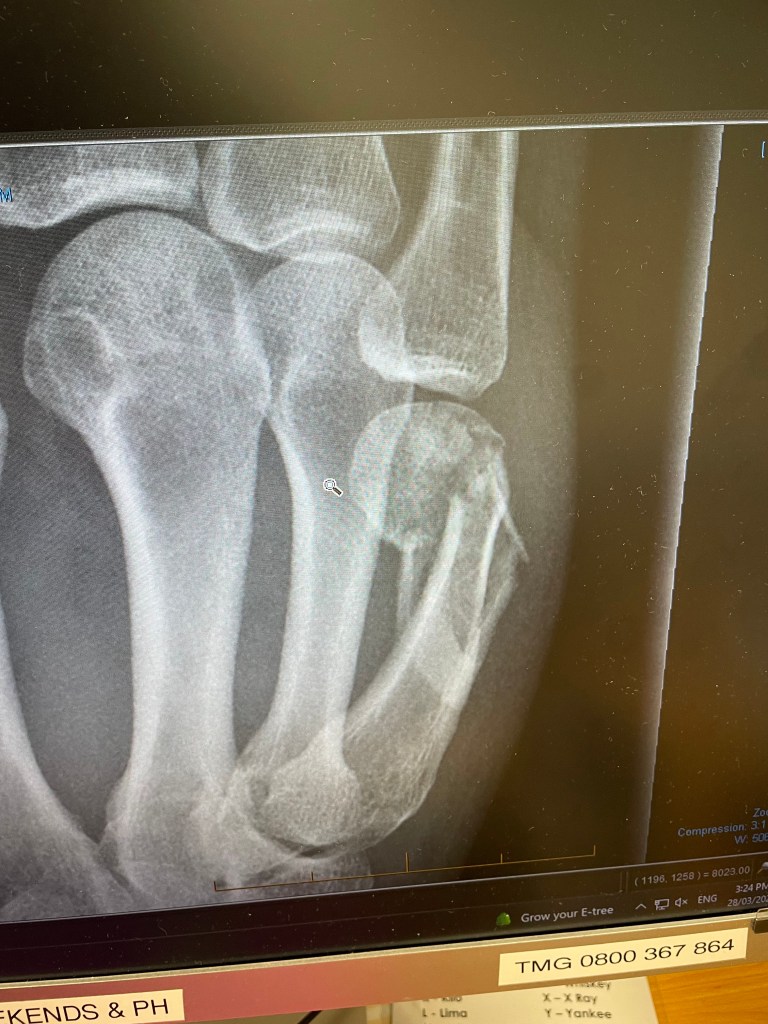

I’ve been back in Pukekohe for just over a week now, and it has been one of ups and downs. I accomplished two things quickly, collecting my new specs and the removal of my cast. The x-ray is not a pretty sight, but the break appears to be healing. Now I can see properly again while trying to get my hand working as it should. Then things slowed down.